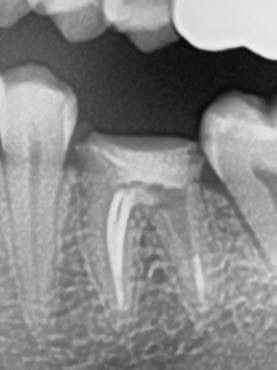

Одномоментная имплантация — Исламов Л.А.(10.11.2025)

Одномоментная имплантация системой Osstem(Ю. Корея), подшит трансплантат с бугра(для увеличения объема мягких тканей), установлен формирователь десны. Через 3 месяца установлена коронка из диоксида циркония на винтовой фиксации